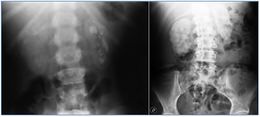

Un médico puede analizar orina y de sangre para verificar si hay concentraciones anormales de sales y minerales. Además, él o ella puede realizar una ecografía o una tomografía computarizada para buscar signos de cálculos renales. Un paciente puede ser referido a un especialista renales para pruebas y confirmar el diagnóstico. Tratamiento